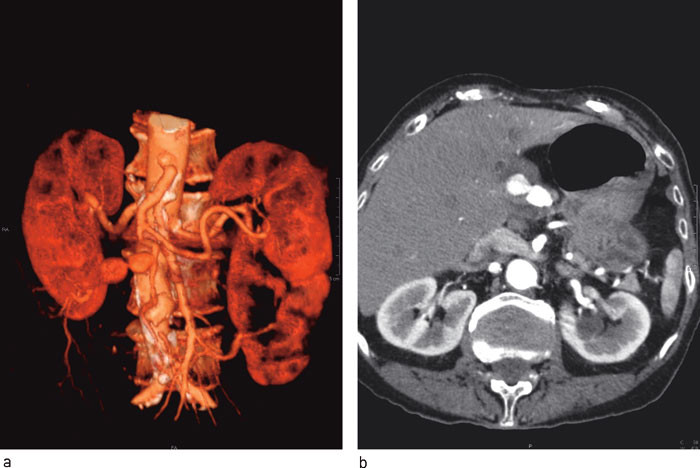

Pasienten ble overflyttet til Rikshospitalet for invasiv koronarutredning. Det ble ikke påvist signifikant koronarsykdom. Funksjonen i venstre ventrikkel ble ansett som god, og hun ble flyttet tilbake til vår avdeling. Her ble det utført CT-undersøkelse som bekreftet mistanken om et aneurisme i forløpet av a. hepatica. Aneurismet ble beskrevet som tobuklet og det var lokalisert ekstrahepatisk svarende til a. hepatica propria, rett etter avgangen av arteria gastroduodenalis. Største diameter ble målt til 3,2 cm. Man fant ikke kontrastfylning perifert for aneurismet (fig 1).

Digital subtraksjonsangiografi viste åpne forhold til og med den proksimale buklen av aneurismet, med åpen a. gastroduodenalis. Det var tilkommet trombosering av den distale buklen av aneurismet (fig 2). Klinisk var pasientens tilstand uforandret, med symptomer som vi tilskrev aneurismet. Det ble ikke registrert stigning i leverfunksjonsprøver.

Hun ble laparatomert via et subkostalt tverrsnitt. Man fant aneurismet lokalisert som forventet. Den mest distalt beliggende del av det tobuklede aneurismet var tynnvegget og trombosert. Den proksimale del var tykkvegget og pulserende. For øvrig var det tydelig puls i a. hepatica sentralt for aneurismet og i a. gastroduodenalis (fig 3). Det var ingen tilbakestrøm av blod fra høyre eller venstre leverarterie. Man vurderte å ligere arteriene proksimalt og distalt for aneurismet, men valgte å bevare sirkulasjonen i a. gastroduodenalis ved å rafe aneurismesekken, som var meget tykk og fibrotisk. Det postoperative forløpet var ukomplisert, uten stigning i leverenzymverdier. Pasienten ble utskrevet etter sju dager uten sine opprinnelige smerter i epigastriet. Histologi viste resektat av aterosklerotisk aneurisme.